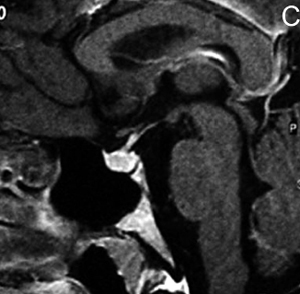

También con la mayor edad se produce involución de la glándula22, lo que puede acentuarse con el desarrollo de una hernia de la cisterna supraselar en la fosa pituitaria, que en grados avanzados constituye un aracnoidocele selar. En estos casos la silla turca puede estar aumentada de tamaño sin que exista un tumor; esto se debe a las pulsaciones del líquido cefalorraquideo(LCR) transmitidos a través de la apertura normal del diafragma selar, que en un 20% de la población puede estar ausente o presentar una dehiscencia adquirida, lo que inicialmente fue descrito en patología como "silla turca vacía"23. Esta situación de vacuidad no es tal, porque en realidad la silla turca está ocupada por líquido cefalorraquideo y una glándula pituitaria aplanada, con un tallo pituitario elongado (Figuras 9A y 9B), condición que se observa con mayor frecuencia en mujeres sobre los 50 años, obesas y multíparas. Se ha descrito en un 5,5 % de las autopsias y generalmente se trata de una condición primaria, habitualmente asintomática. En los casos secundarios, cuando hay causas como la cirugía o radioterapia, puede asociarse con alteraciones del campo visual por adherencias que deforman el quiasma óptico24.

Figura 9A y B. Cortes sagitales, secuencias T1wl con Gadolinio y T2w, muestran la hipófisis en la porción inferior de la fosa pituitaria, lo que es secundario a una herniación de la cisterna supraselar (flecha). Obsérvese que el tallo pituitario esta también descendido. La secuencia T2w permite confirmar que la señal del líquido en la fosa pituitaria es similar al LCR del IV ventrículo (punta de flecha). Tumores pituitarios